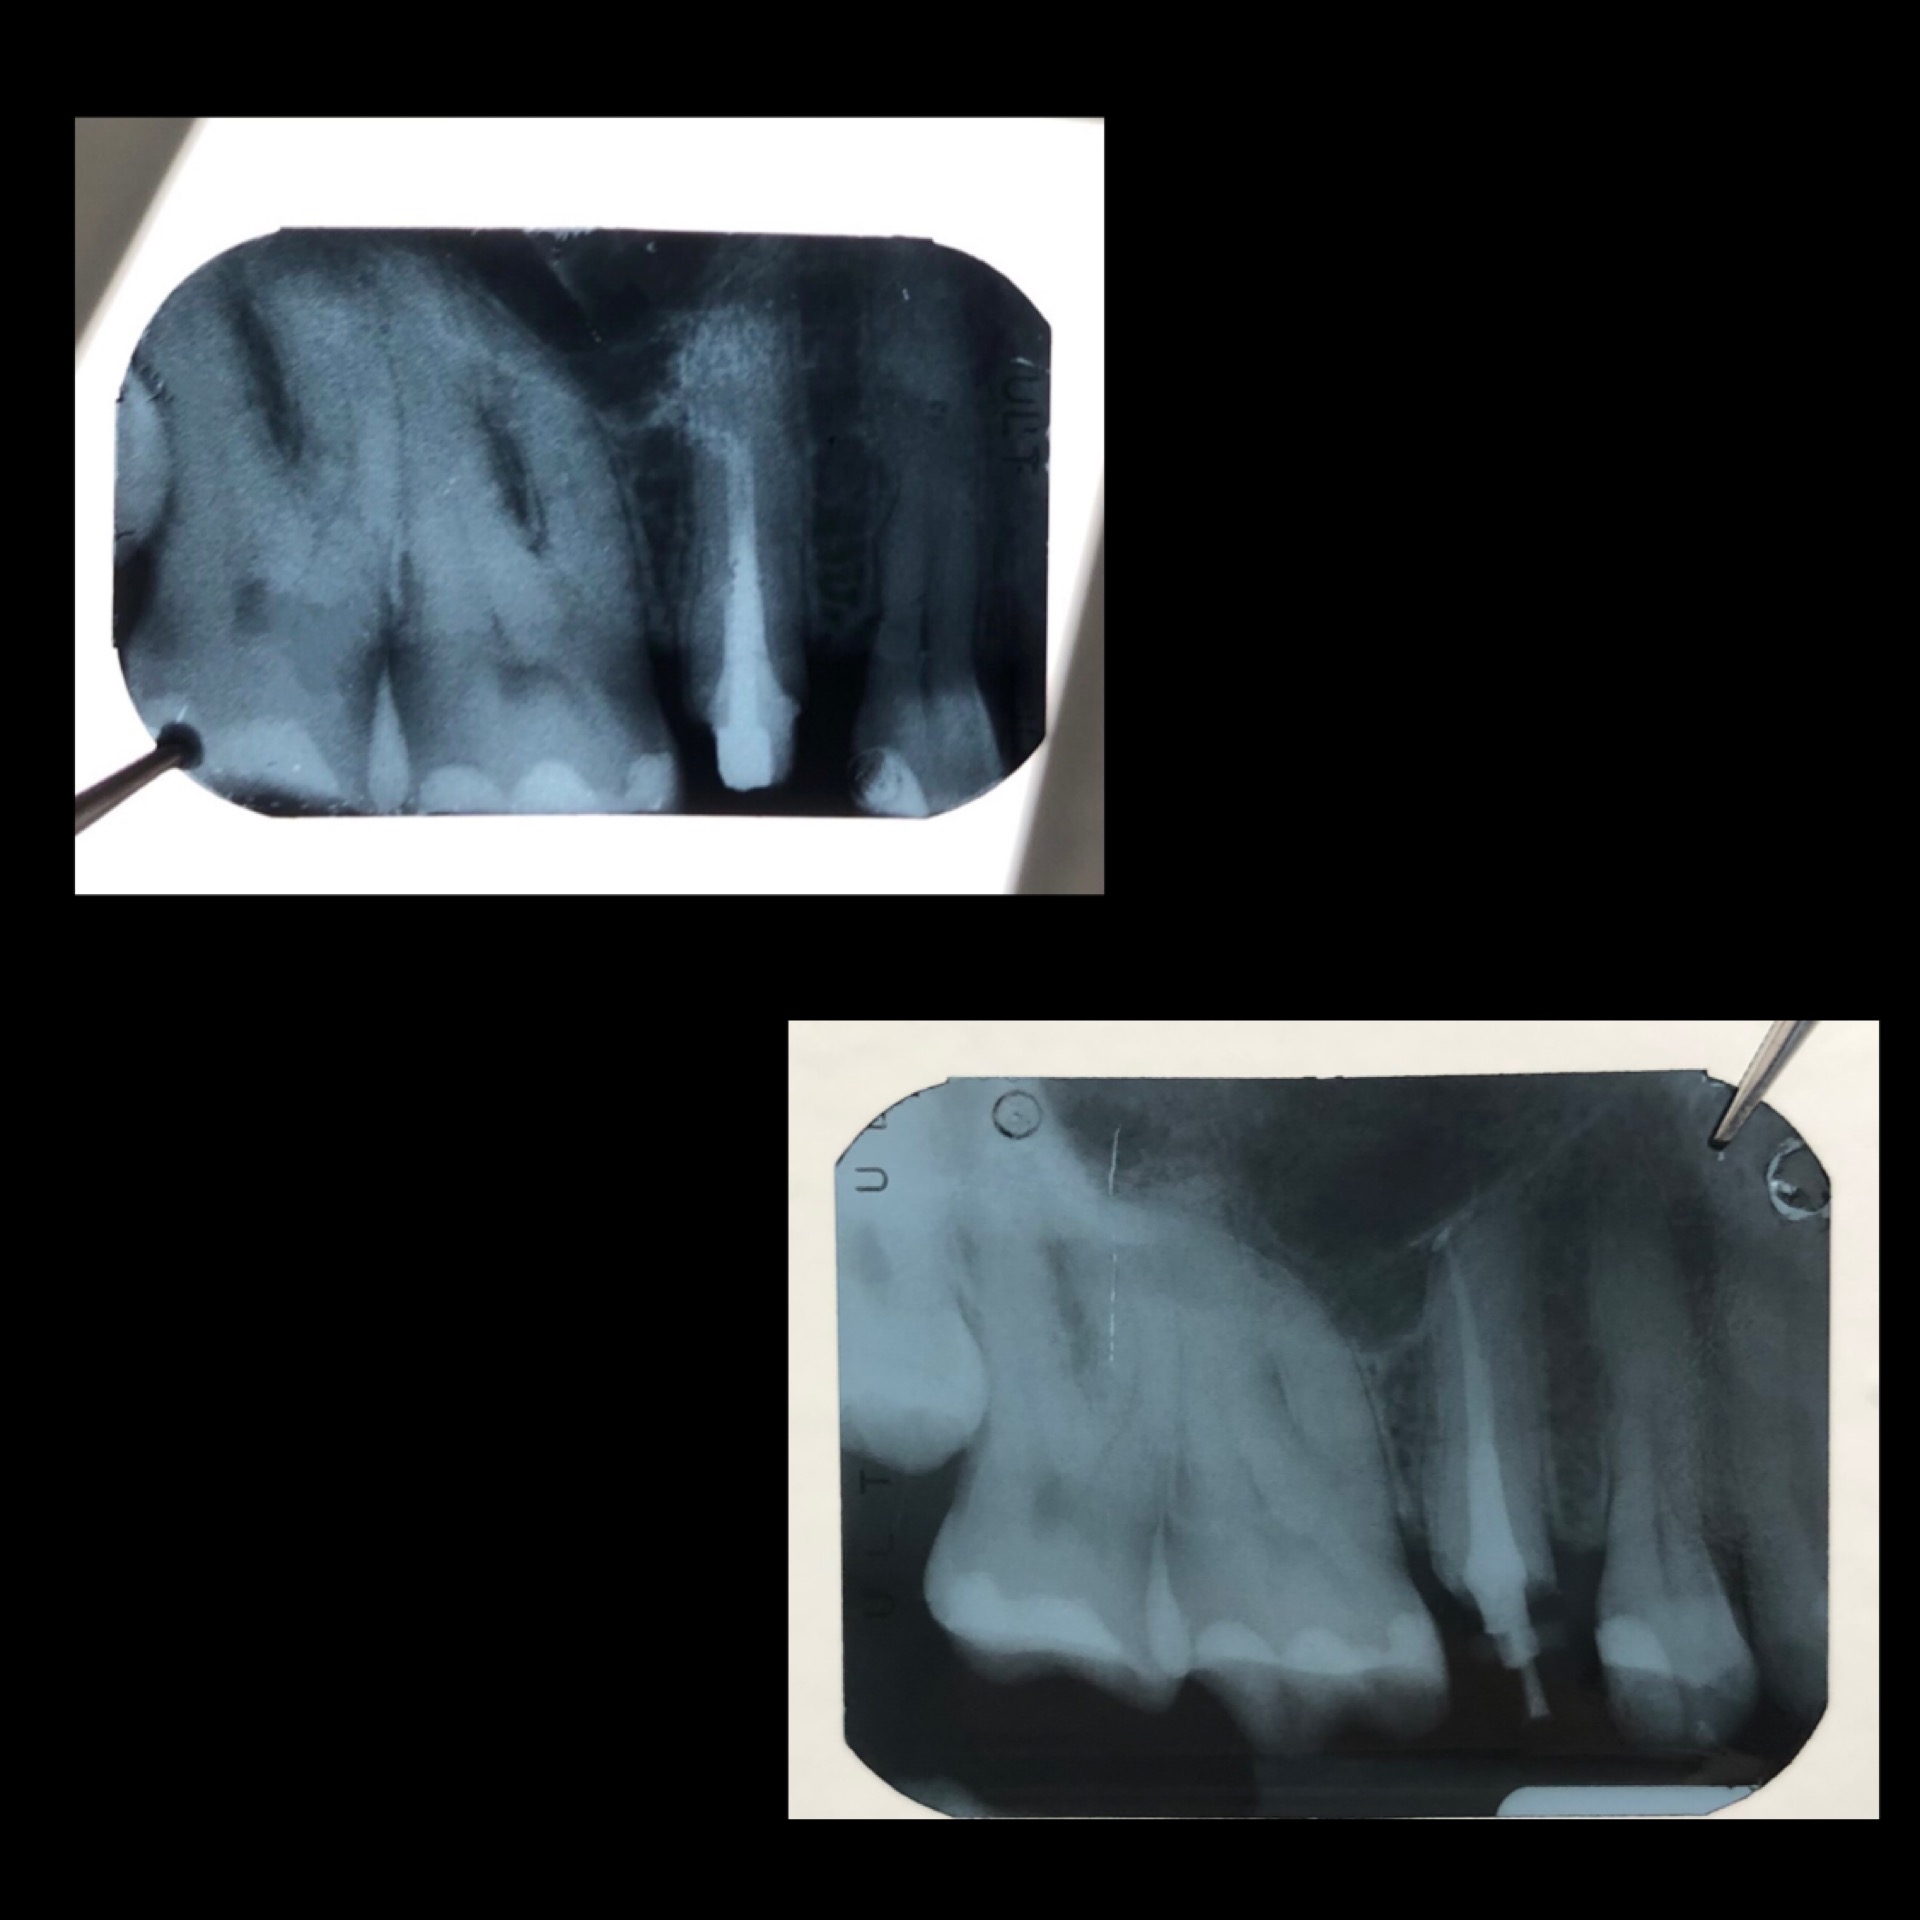

Una corretta terapia canalare con un perfetto sigillo a livello degli apici delle radici è fondamentale. I denti devitalizzati impropriamente possono creare ulteriori problemi che poi andranno a ripercuotersi sulle cure effettuate successivamente come le ricostruzioni e le corone protesiche con conseguente fallimento del piano terapeutico.

Capita spesso di incontrare denti già devitalizzati in maniera impropria che necessitano, seppur asintomatici, di essere ritrattati per evitare che i granulomi infetti visibili radiograficamente si evolvano riassorbendo tutto l’osso sottostante.